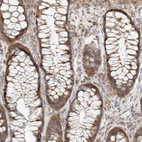

Immunohistochemical staining of human testis shows strong cytoplasmic positivity in cells in seminiferous ducts.